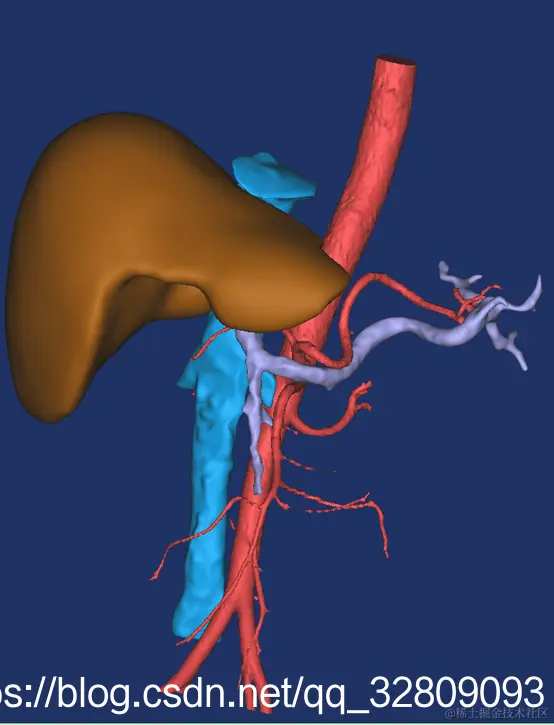

最后建模出来的效果:

正面图(肝脏+动脉+门静脉+腔静脉)                                反面图                                                          透视图